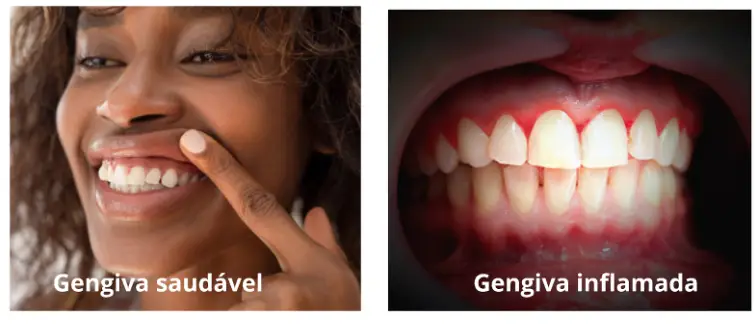

Doenças periodontais: O estresse enfraquece o sistema imunológico, tornando o organismo mais suscetível a infecções como gengivite e periodontite, que podem levar à

perda dos dentes se não tratadas.

Gengivas inchadas e vermelhas